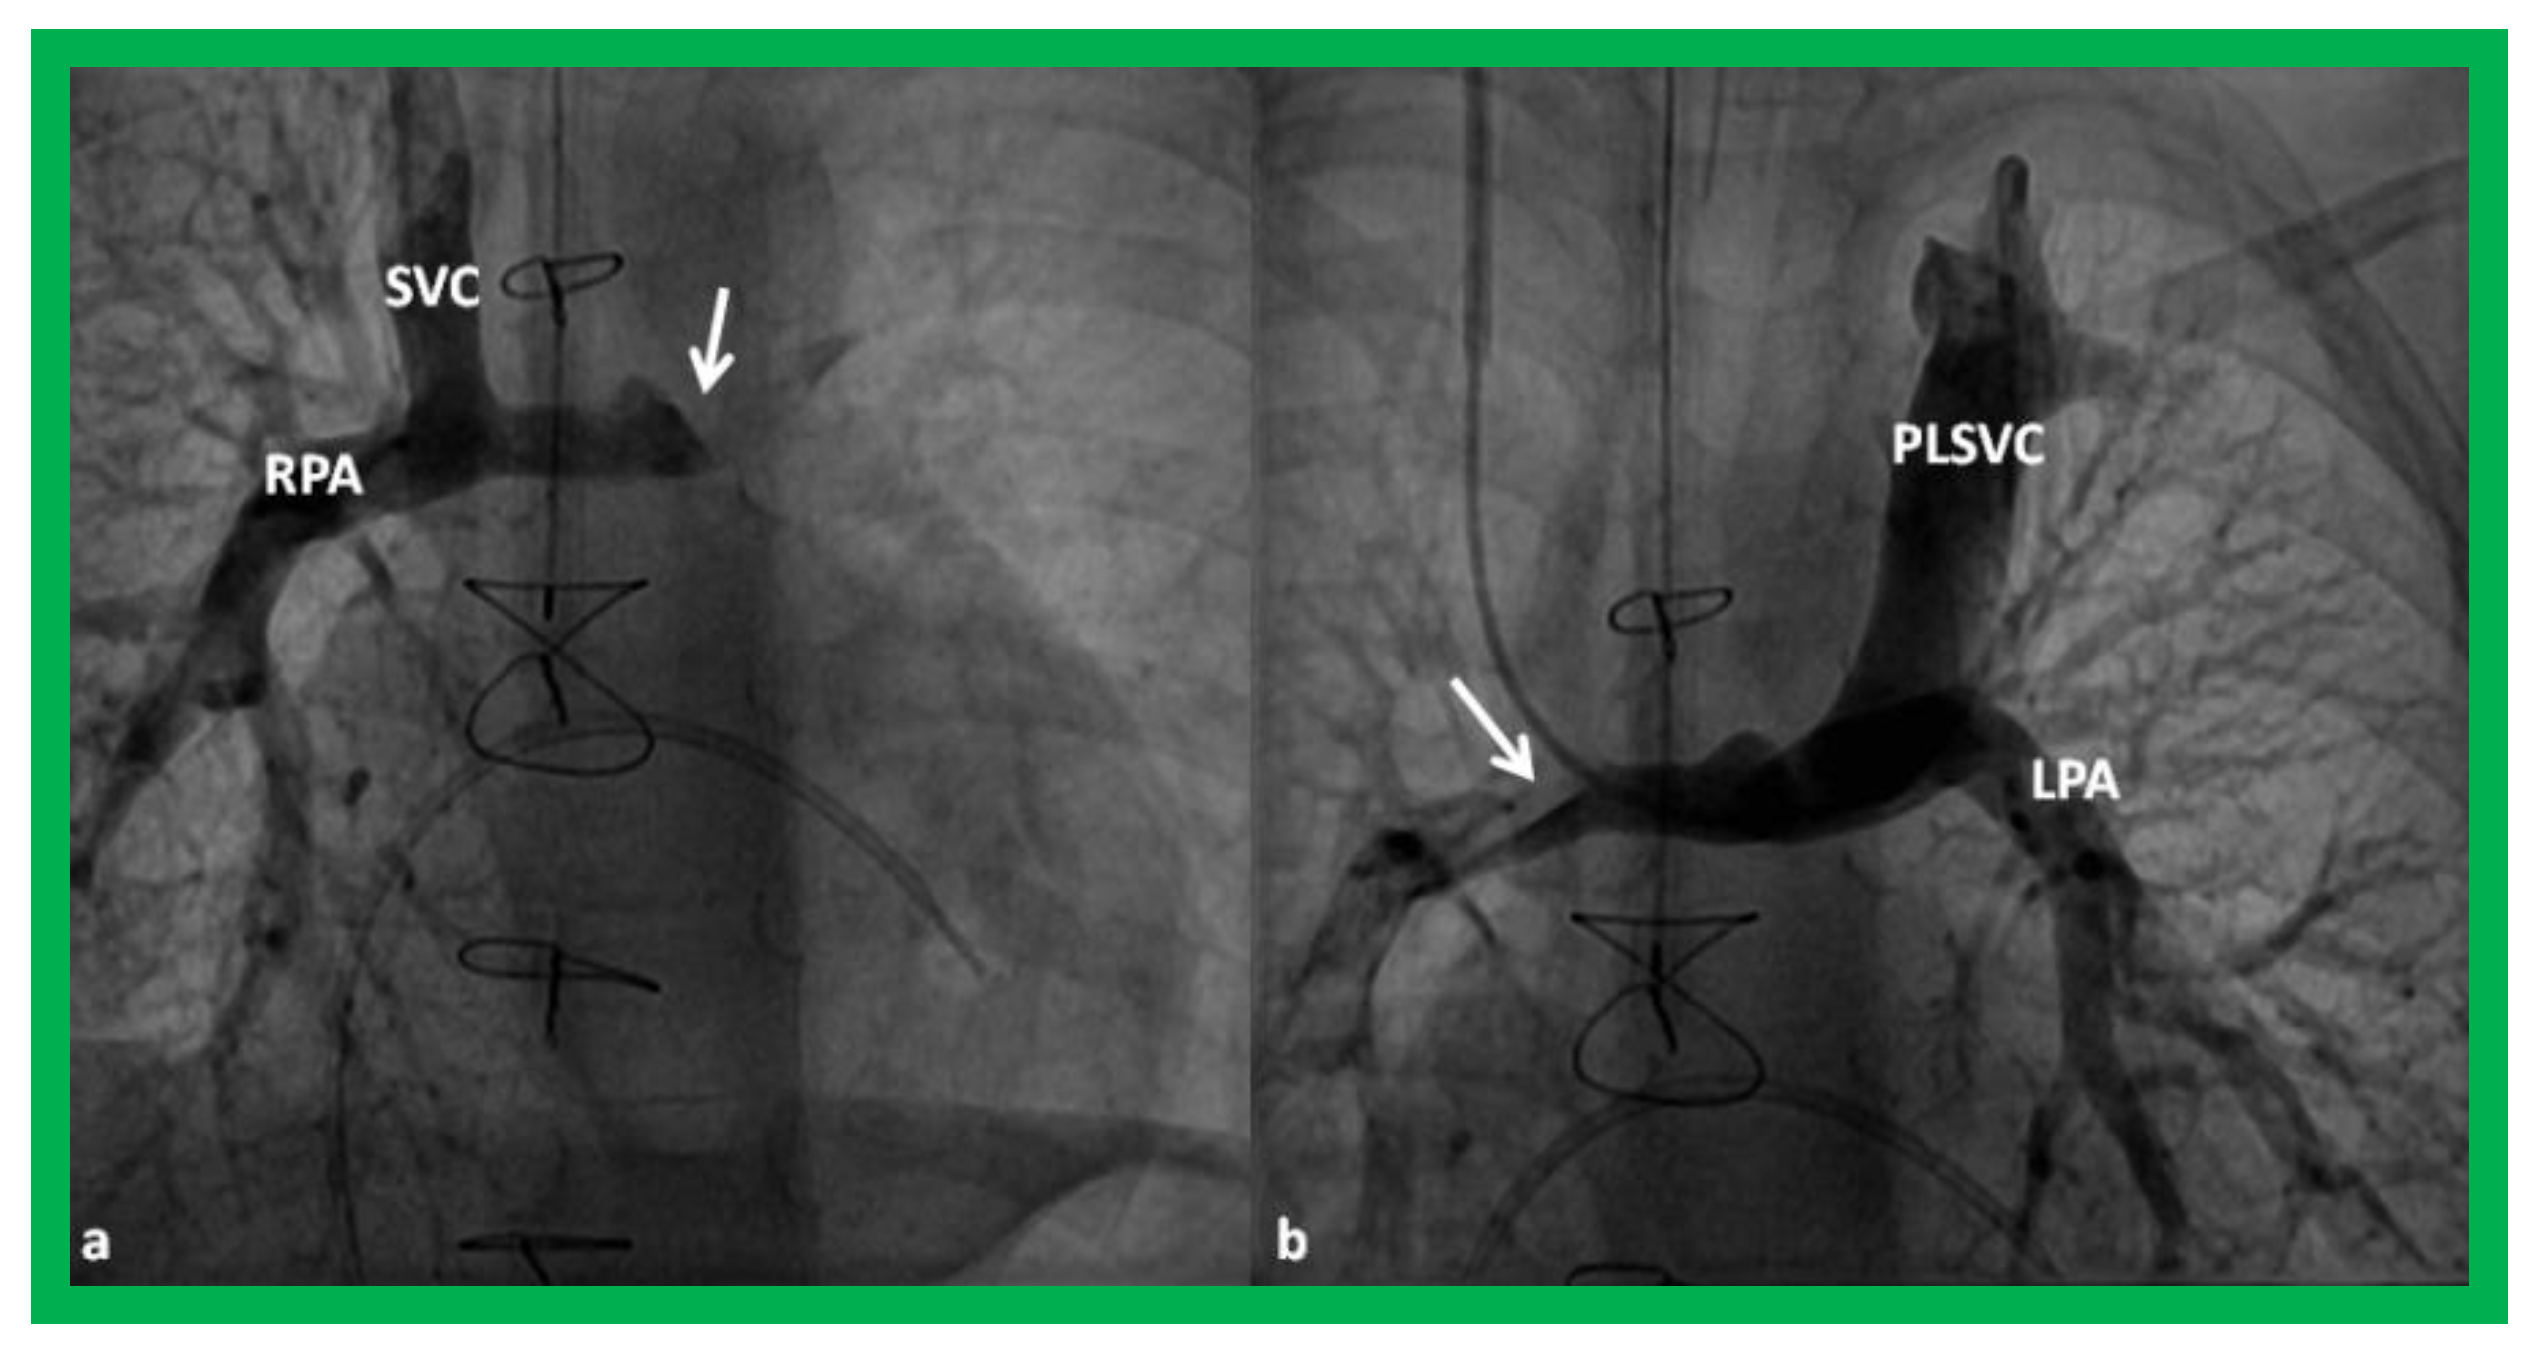

In babies who have persistent left SVC, bilateral bidirectional Glenn (Figure 15) is performed particularly in patients with a small or absent left innominate vein. A bidirectional Glenn procedure may also be undertaken for patients with infrahepatic interruption of the IVC with azygos or hemiazygos continuation, and such a procedure may be called the Kawashima procedure.

Figure 15.

Cineangiographic frames demonstrating a bilateral bidirectional Glenn procedure (Stage II). In (a), angiogram of the superior vena cava (SVC) illustrates opacification of the right pulmonary artery (RPA). The arrow in (a) shows the unopacified blood from a persistent left superior vena cava (PLSVC). In (b), an injection into the PLSVC illustrates opacification of the left pulmonary artery (LPA). The arrow in (b) shows the unopacified blood from the right SVC. Unobstructed flow from the respective SVCs into the pulmonary arteries is clearly seen. Reproduced from Reference [33].